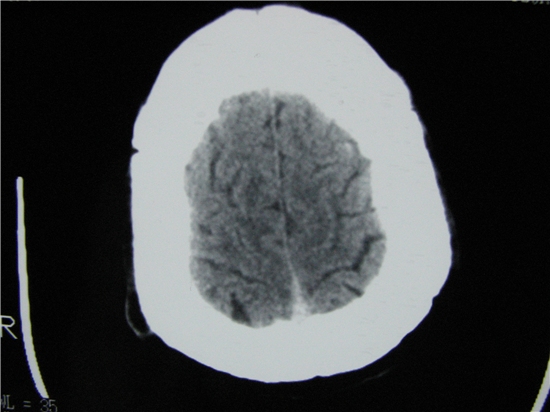

标题: CT23231:男 32岁 车祸伤,鼻腔内出血明显。 [打印本页]

标题: CT23231:男 32岁 车祸伤,鼻腔内出血明显。

额窦内及额部软组织内可见多发游离类骨质密度影,考虑额骨骨折可能。

鼻骨层面较少,无法判断鼻骨。

左侧额骨、鼻骨骨折,头面部软组织肿胀。

左侧额骨、鼻骨骨折,额窦内的应该是游离骨块